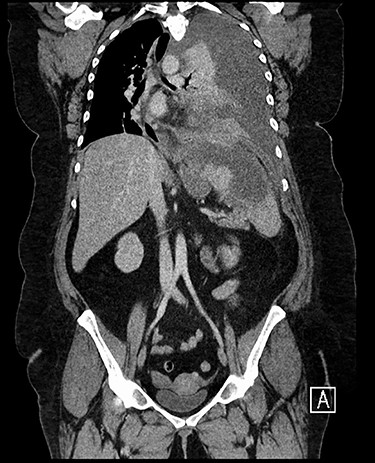

Forty-four-year-old clinically obese woman whose only past medical history was mild asthma with no use of systemic steroids. Initially presented with parapneumocic effusion following a recent bout of pneumonia which was not amenable to aspiration. Prior to this, the patient had experienced vague abdominal symptoms 1 month prior to the onset of the pneumonia. She was treated with oral amoxicillin. Twenty-five days later, she presented again in the Accident & Emergency Department with left-sided chest pain, left flank pain associated with fever and worsening dyspnea. Computed tomography (CT) scan (Fig. 1) showed a significant left-sided effusion with a complete collapse of the left lung and mild mediastinal shift towards the right. A 12.5 cm collection in the upper pole of the spleen was noted which appeared to extend through the diaphragm (Fig. 2). She was started on the sepsis pathway as per hospital protocol. A seldinger chest drain was inserted which immediately drained 1500 ml of pus. She underwent a thoracoscopic washout, debridement and decortication. The chest drains were removed 9 days post-operatively. She was transferred to General surgeons where a percutaneous drain (pigtail catheter) was inserted under ultrasound guidance. Three hundred and five milliliters in a total of pus was drained from the splenic abscess. Staphylococcus aureus was isolated from both the pleural and splenic collection. Blood cultures and transthoracic echocardiogram were unrevealing. A blood bourne virus screen (Hepatitis B, Hepatitis C, HIV) was negative as well. A repeat ultrasound scan showed complete resolution of the splenic abscess with normal splenic architecture.

CT chest, abdomen and pelvis sagittal view: left-sided empyema and splenic abscess.